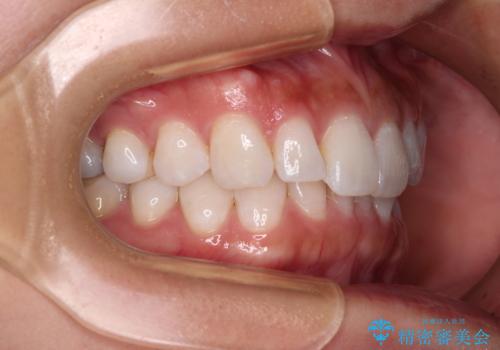

【モニター】前歯のデコボコと小さい前歯 インビザライン矯正とオールセラミッククラウン補綴治療

- 前歯の歯並びと生えてきたときから小さい前歯を気にして来院された患者様です。

上下前歯の歯列不正はインビザラインにより整え、その後に、矮小歯の前歯をオーダーメイドタイプのオールセラミッククラウンにて補綴治療することとしました。

インビザライン矯正の場合、矮小歯を矯正治療後にセラミックとするかどうかを矯正治療開始前に決める必要があるため、悩んでしまう方が多いです。

セラミッククラウンにて大きさを変更することを前提に矯正治療を開始したため、大変満足のいく仕上がりとなりました。